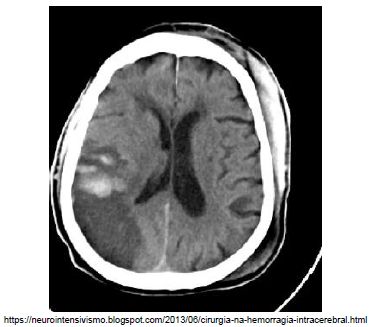

Analise a imagem a seguir.

A lesão isquêmico-hemorrágica presente nessa imagem foi determinada por injúria de qual artéria?